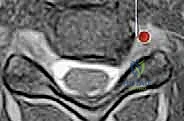

- التصوير بالرنين المغناطيسي (MRI): وهو الفحص الأهم لتحديد موقع الانزلاق الغضروفي بدقة ومدى انضغاط الأعصاب.

- الأشعة السينية (X-rays): لتقييم الهيكل العظمي والاصطفاف الفقري.

- التصوير المقطعي (CT Scan): قد يُطلب للحصول على تفاصيل أدق للتشريح العظمي.

الخطوة 3: تحديد مستوى الإصابة بدقة

باستخدام جهاز الأشعة السينية الفلوروسكوبي (Fluoroscopy) داخل غرفة العمليات، يتأكد الدكتور هطيف من الوصول إلى القرص التالف بدقة مليمترية.